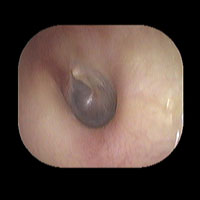

左急性中耳炎(重症)

鼓膜がやや赤くなって腫れています。鼓膜の奥に膿が透けて見えています。抗生剤の内服で鼓膜切開を行わずに22日目で治りました。

14日目